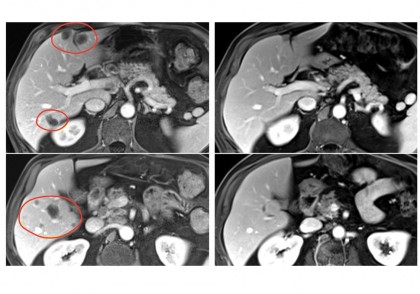

Frank J. Lowery, Stephanie L. Goff, Billel Gasmi, Maria R. Parkhurst, Nivedita M. Ratnam, Hyunmi K. Halas, Thomas E. Shelton, Michelle M. Langhan, Aarushi Bhasin, Aaron J. Dinerman, Victoria Dulemba, Ian S. Goldlust, Alexandra M. Gustafson, Abraham A. Hakim, Kyle J. Hitscherich, Lisa M. Kenney, Lior Levy, Juliette G. Rault-Wang, Alakesh Bera, Satyajit Ray, Courtney D. Seavey, Chuong D. Hoang, Jonathan M. Hernandez, Jared J. Gartner, Sivasish Sindiri, Todd D. Prickett, Lori S. McIntyre, Sri Krishna, Paul F. Robbins, Nicholas D. Klemen, Mei Li M. Kwong, James C. Yang, Steven A. Rosenberg. Neoantigen-specific tumor-infiltrating lymphocytes in gastrointestinal cancers: a phase 2 trial. Nature Medicine, 2025; DOI: 10.1038/s41591-025-03627-5Foto: Center for Cancer Research/National Cancer Institute